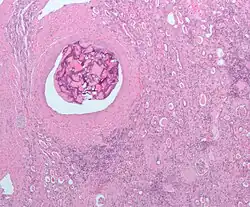

| Micrograph of embolic material in the artery of a kidney. The kidney was surgically removed because of cancer. H&E stain. | |

An embolism is the lodging of an embolus, a blockage-causing piece of material, inside a blood vessel.[1] The embolus may be a blood clot (thrombus), a fat globule (fat embolism), a bubble of air or other gas (gas embolism), amniotic fluid (amniotic fluid embolism), or foreign material.